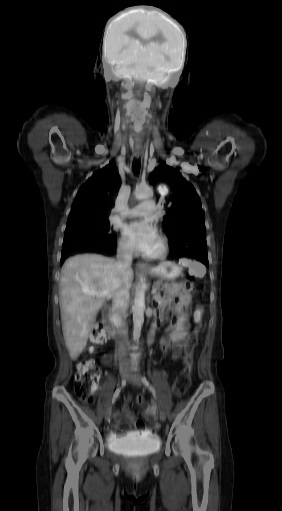

Die ein­zel­nen Kör­per­re­gio­nen wer­den mit­tels einem Computertomographen dar­ge­stellt. Es wer­den die je­wei­li­gen Kör­per­re­gio­nen in Un­ter­mo­du­len ab­ge­han­delt.